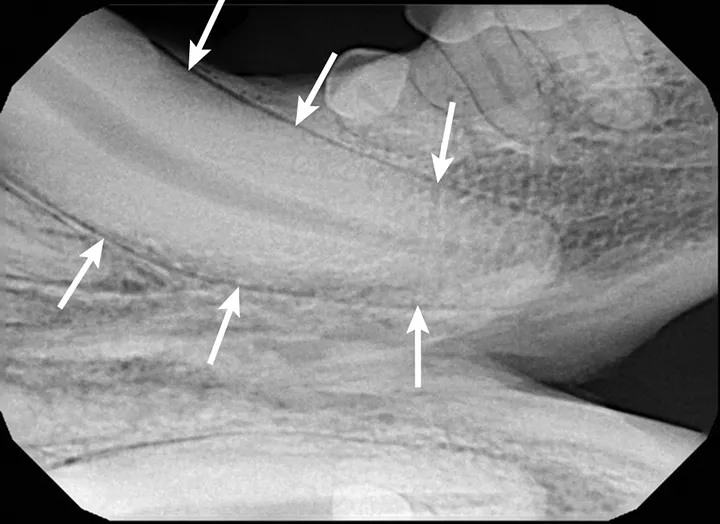

FIGURE 1A

Patient positioned in lateral recumbency; the bisecting angle technique is used to obtain radiographs of the right maxillary fourth premolar (A). The plate or film should be parallel to the hard palate (white line). The direction of the tooth root to be imaged is represented by a black line. An imaginary line can be drawn halfway between the angle of the plate or film and tooth roots (ie, bisecting angle [gray line]), usually a 45-degree angle for the maxilla. The beam (ie, x-ray tube head) should be oriented perpendicular to the bisecting angle (gray line) so the actual size of the tooth is shown (B); a crown fracture with suspected pulp exposure is visible (arrow), and radiolucency can be seen around the apex of the distal root (arrowheads).